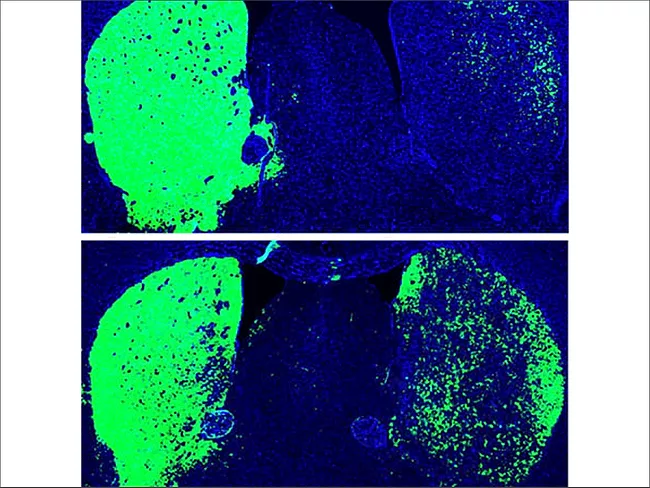

Dopaminergic neurons

ISSCR 2020: In-brain direct reprogramming creates neurons, alleviates Parkinson’s

June 30, 2020

By Anette Breindl

Two separate groups have recently shown that in mouse models, inactivation of a single gene was enough to directly convert other cell types in the brain into neurons.

Read More